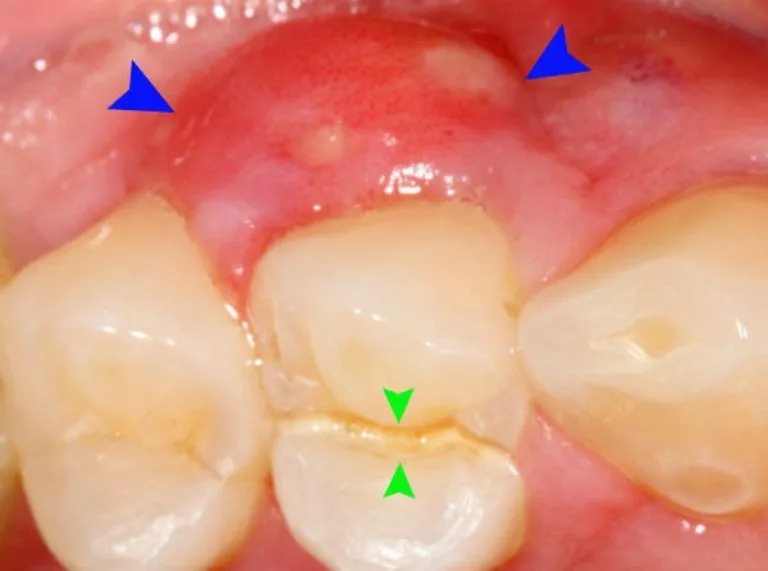

Viêm nướu răng là một trong những vấn đề răng miệng phổ biến, đặc biệt ở trẻ em. Khi nói đến hình ảnh viêm nướu răng ở